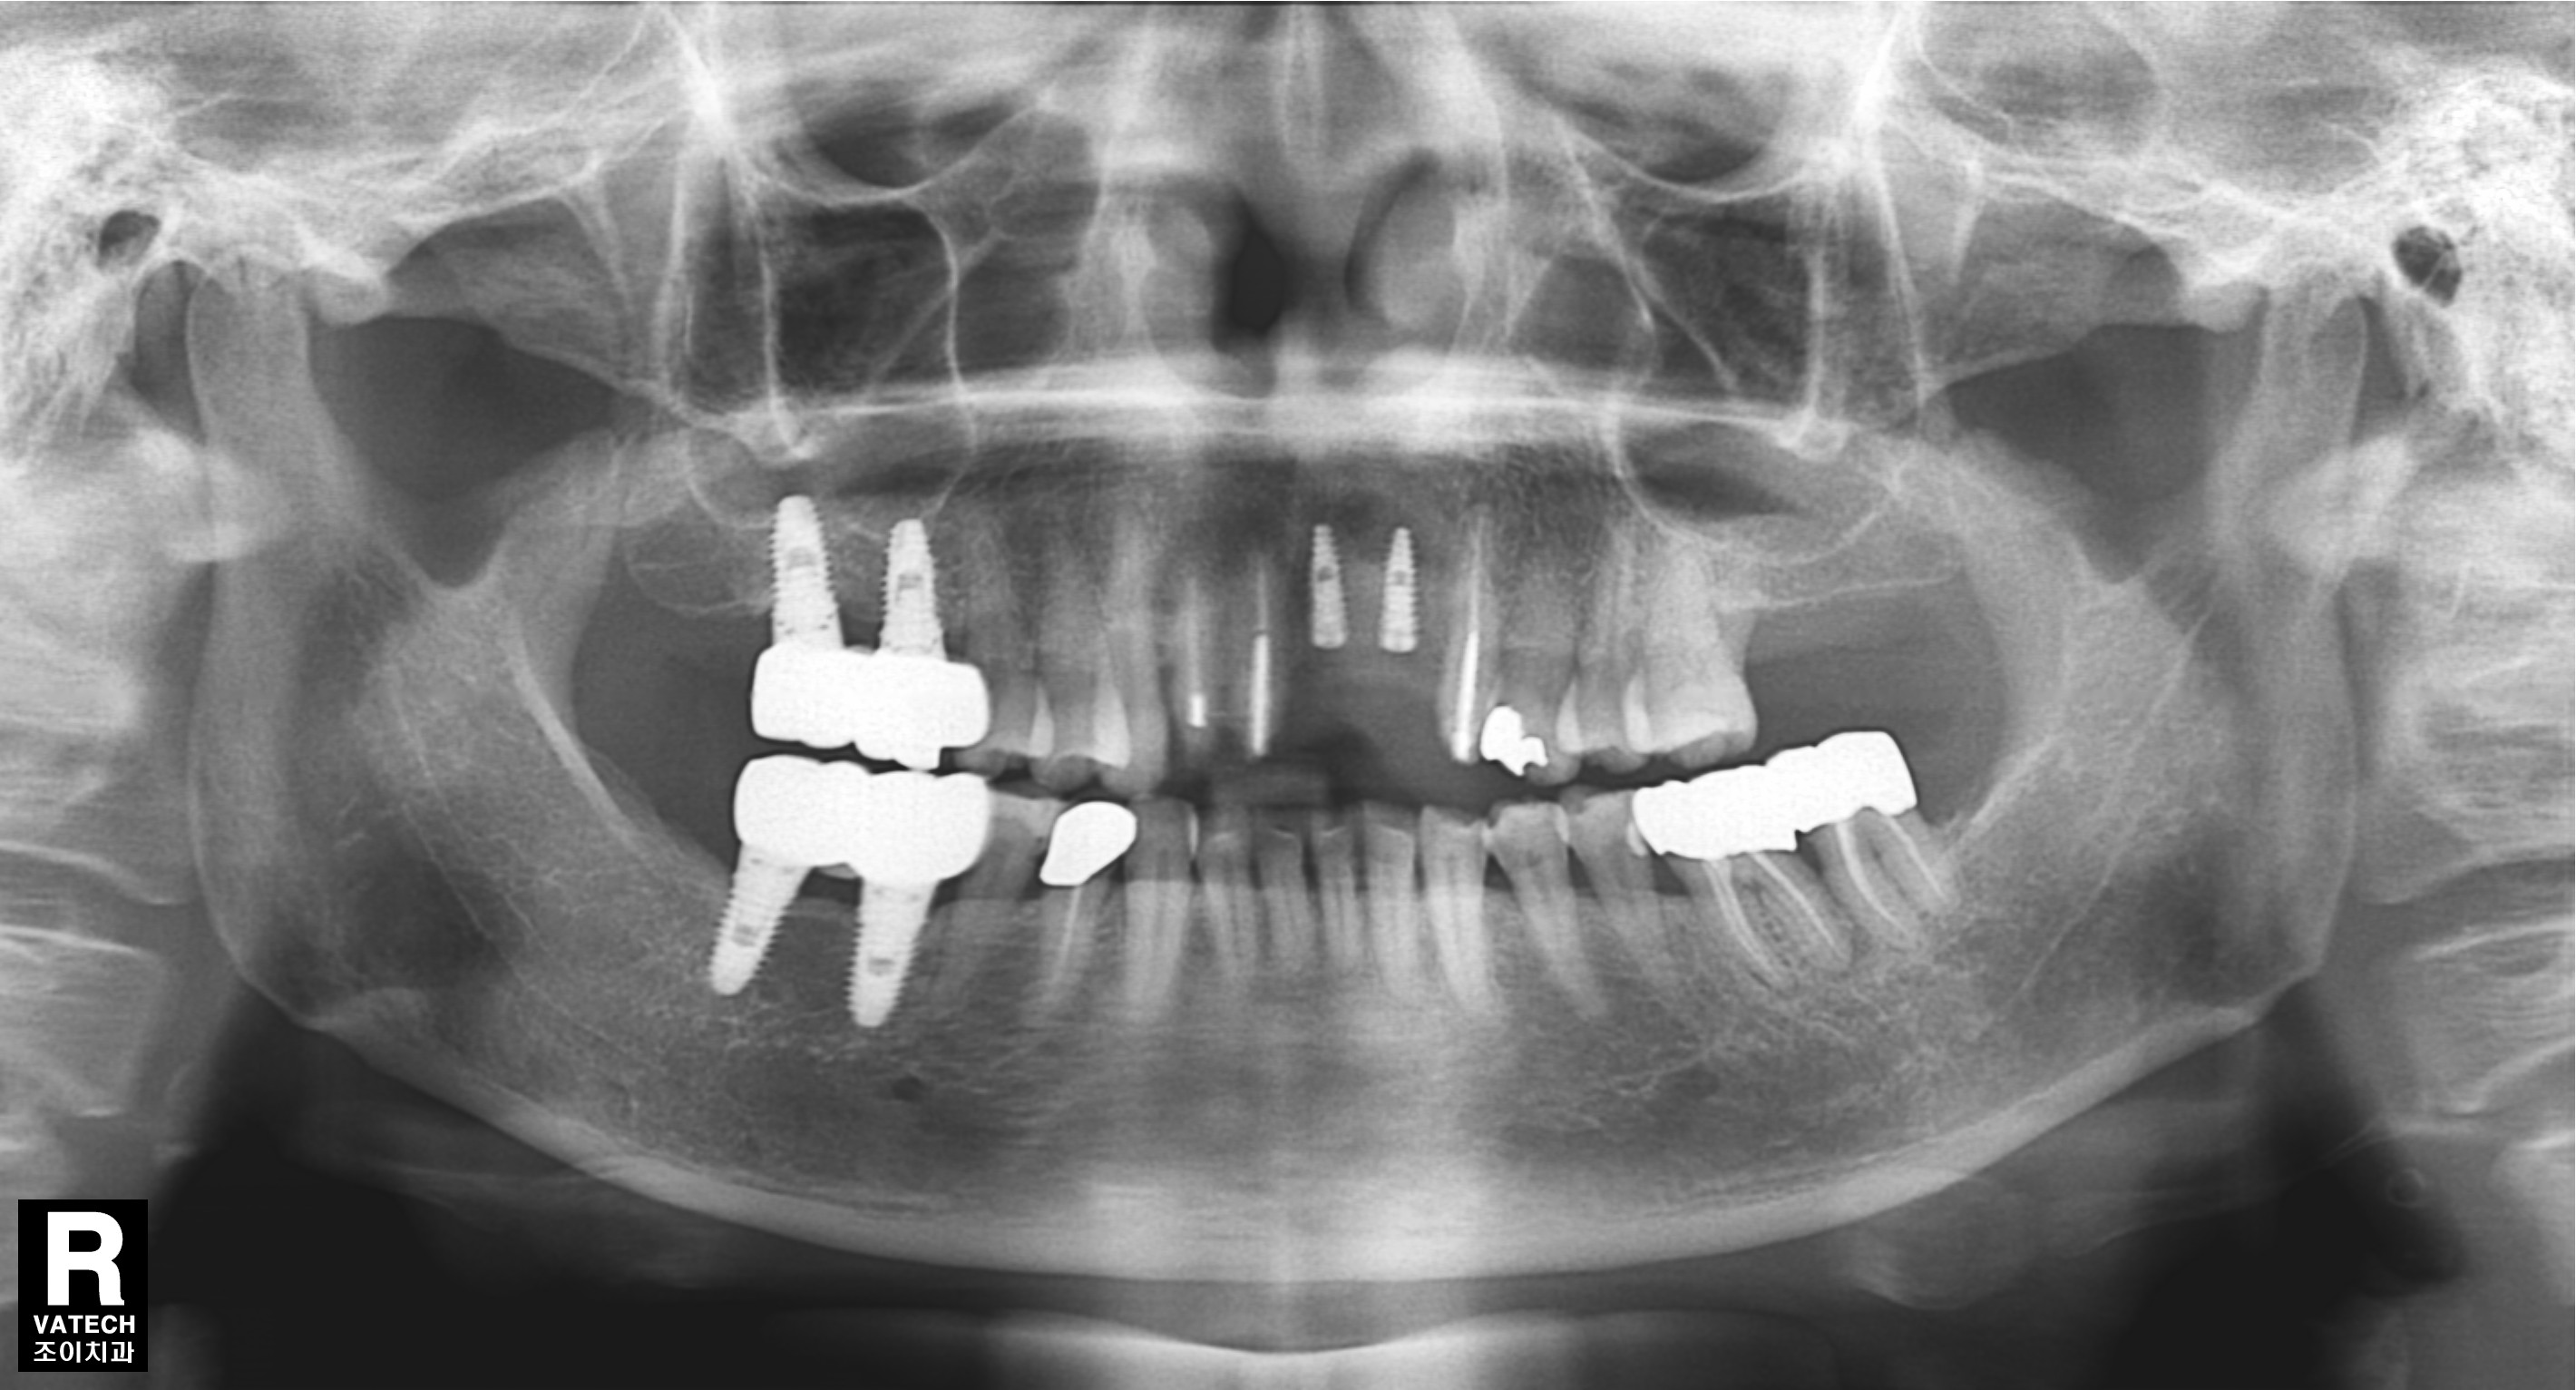

[임플란트] 제목 : 임플란트와 보철치료의 결합

오래된 보철의 파절로 일부는 임플란트로 일부는 치아 재보철로 치료하였습니다.